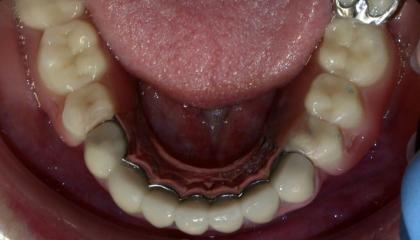

Partial denture with precision attachments